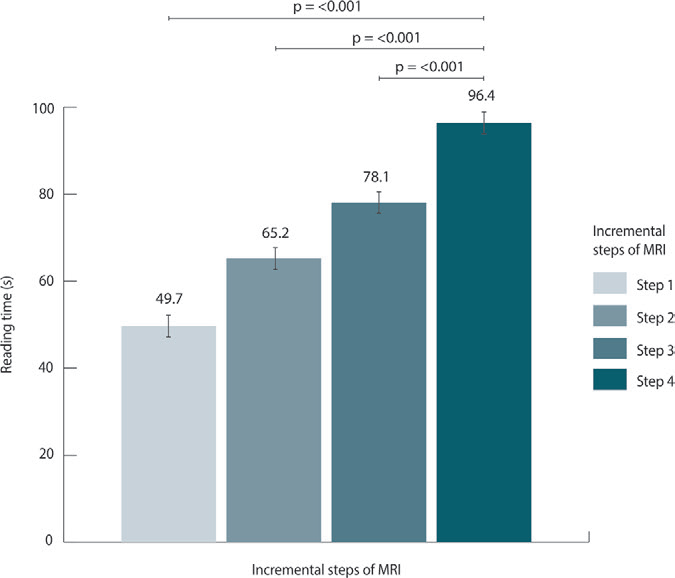

- 阅读时间:Step 1(49.7 秒) vs Step 4(96.4 秒),缩短 48%(P<0.001);